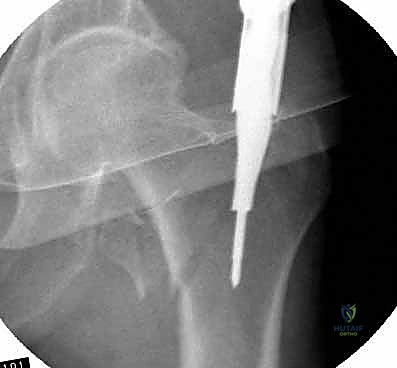

2. الأشعة السينية (X-Rays): هي المعيار الذهبي والأول للتشخيص. يتم أخذ صور من زوايا متعددة (أمامي خلفي وجانبي) لتحديد موقع الكسر، ونوعه، ودرجة تفتت العظام.

3. الأشعة المقطعية (CT Scan): يطلبها الدكتور هطيف في حالات الكسور المعقدة والمتفتتة جداً، حيث توفر صورة ثلاثية الأبعاد تساعد في التخطيط الجراحي الدقيق واختيار حجم المسمار المناسب.

باستخدام جهاز الأشعة السينية المرئية المستمرة (C-Arm Fluoroscopy) داخل غرفة العمليات، يقوم الدكتور هطيف بإعادة العظام المكسورة إلى محاذاتها التشريحية الصحيحة عن طريق الشد والتدوير الخارجي للساق، وكل ذلك يتم مراقبته على الشاشة بدقة متناهية.